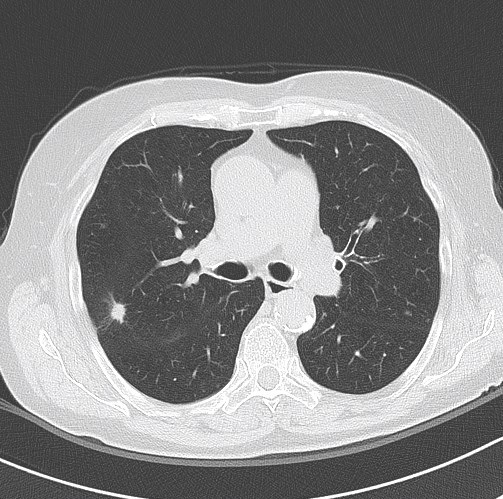

Lung function tests: vital capacity 4930 ml (110%), FEV1 2720 ml (79%), TI 55%, diffusion capacity 81%. There was no response in FEV1 to bronchodilator challenge test. On the CT scan a solitary 12 mm spiculate lesion was discovered in the 3rd segment of the right upper lobe near the interlobar fissure, suspicious for primary long tumor. No metastases or enlarged lymph nodes were observed. Additionally, moderate centrilobular emphysema was described.

CT-scan – lesion in the 3rd segment of the right upper lobe (axial, coronal and sagittal reconstruction)